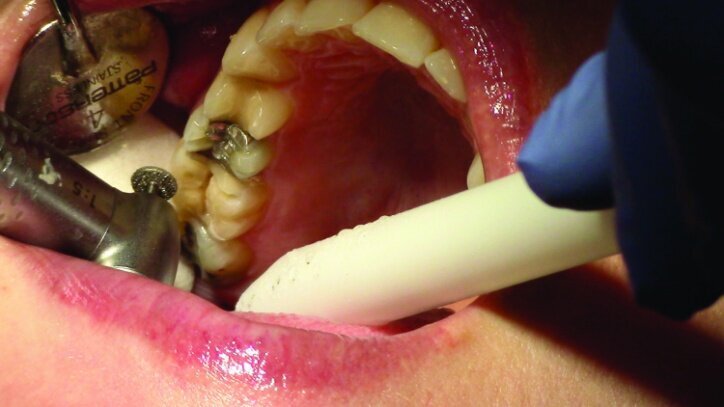

This patient presented for restorations of teeth #3 and #4 (Fig. 1a). Because of the size of the existing restorations, these teeth were diagnosed as structurally compromised (Figs. 1b, c). The prognosis without treatment was fair.

The restorations were to be completed with PlanScan chairside CAD/CAM technology in the same visit.

Depth guide cuts were made using a 330 bur, which has a 2 mm cutting surface (Figs. 2a–3b). This ensures 2 mm of occlusal reduction to accommodate 2 mm of material thickness on the occlusal surface of the restoration.